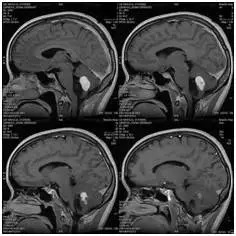

中国MRI技术:

1985年,中国引进了第一台MRI

1986年底,中国科学院通过与美国高科技公司合作,在深圳蛇口成立了安科高技术股份有限公司;

1988年,安科成功开发出中国第一台磁共振成像系统:场强为0.15T的永磁型MRI――ASP-015样机;

1989年底,中国第一台获批磁共振成像系统正式在安科诞生;

▲ 中国第一台自主研发的磁共振设备